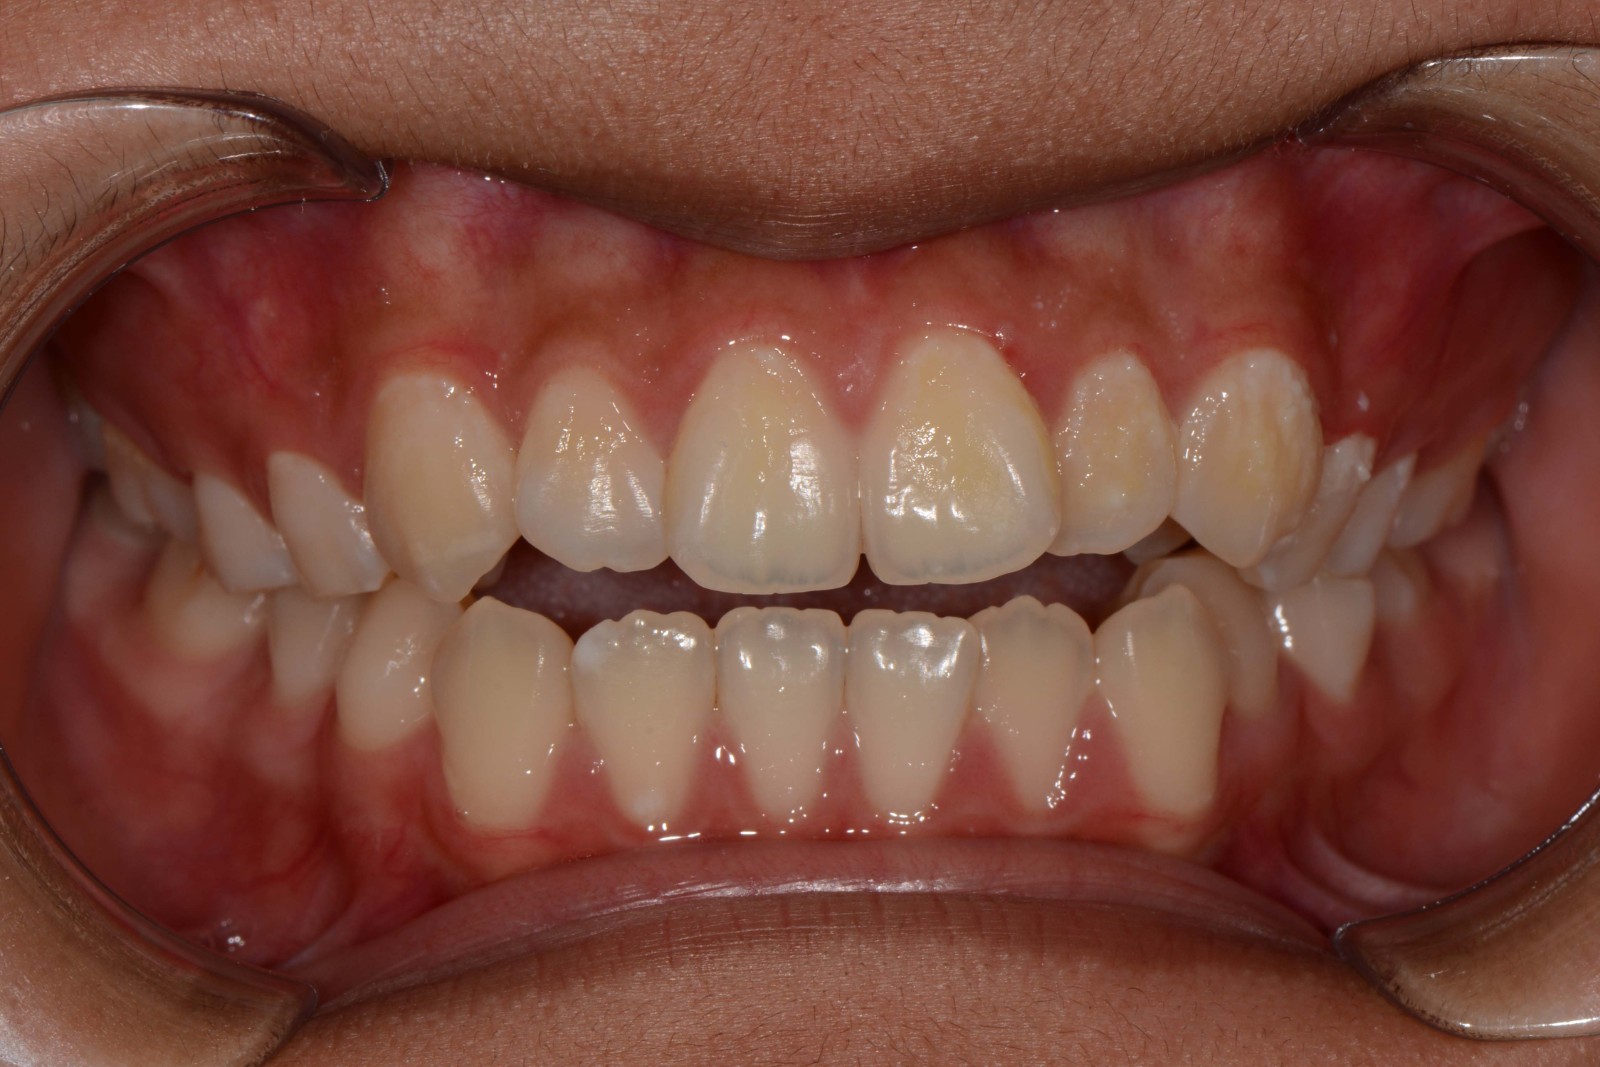

患者:14岁女性

主诉:前牙咬不住,进食不便

前牙区开颌3mm

诊断:安氏II类错颌畸形  开颌

矫治前: